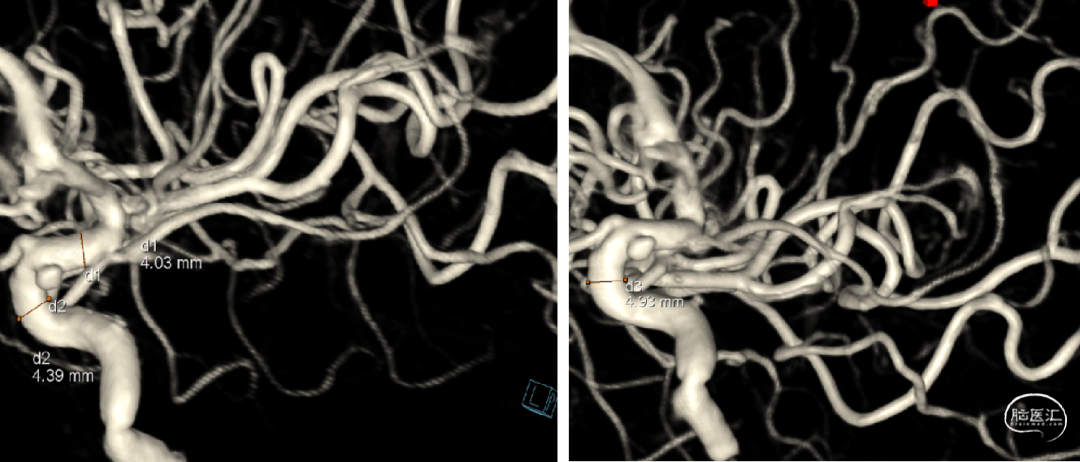

•DSA手术规划:选择麒麟血流导向装置4.0x20

2024年4月全身麻醉下经股血流导向密网支架置入术

选择Lattice4.7x18